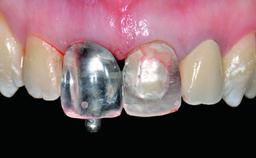

In 2008, a healthy 15-year-old female, non-smoking patient presented at our clinic with a major esthetic problem of tooth 21. Her dental history revealed that the tooth had been avulsed by trauma years before. As a result, the replanted and temporarily splinted tooth had ankylosed and was in severe apical malposition. The ankylosed tooth exhibited a significant gingival recession that disturbed the patient greatly. Due to the patient’s low age and with her skeletal growth not completed, periodic follow-up visits were scheduled to monitor the situation until the patient was old enough for implant therapy.